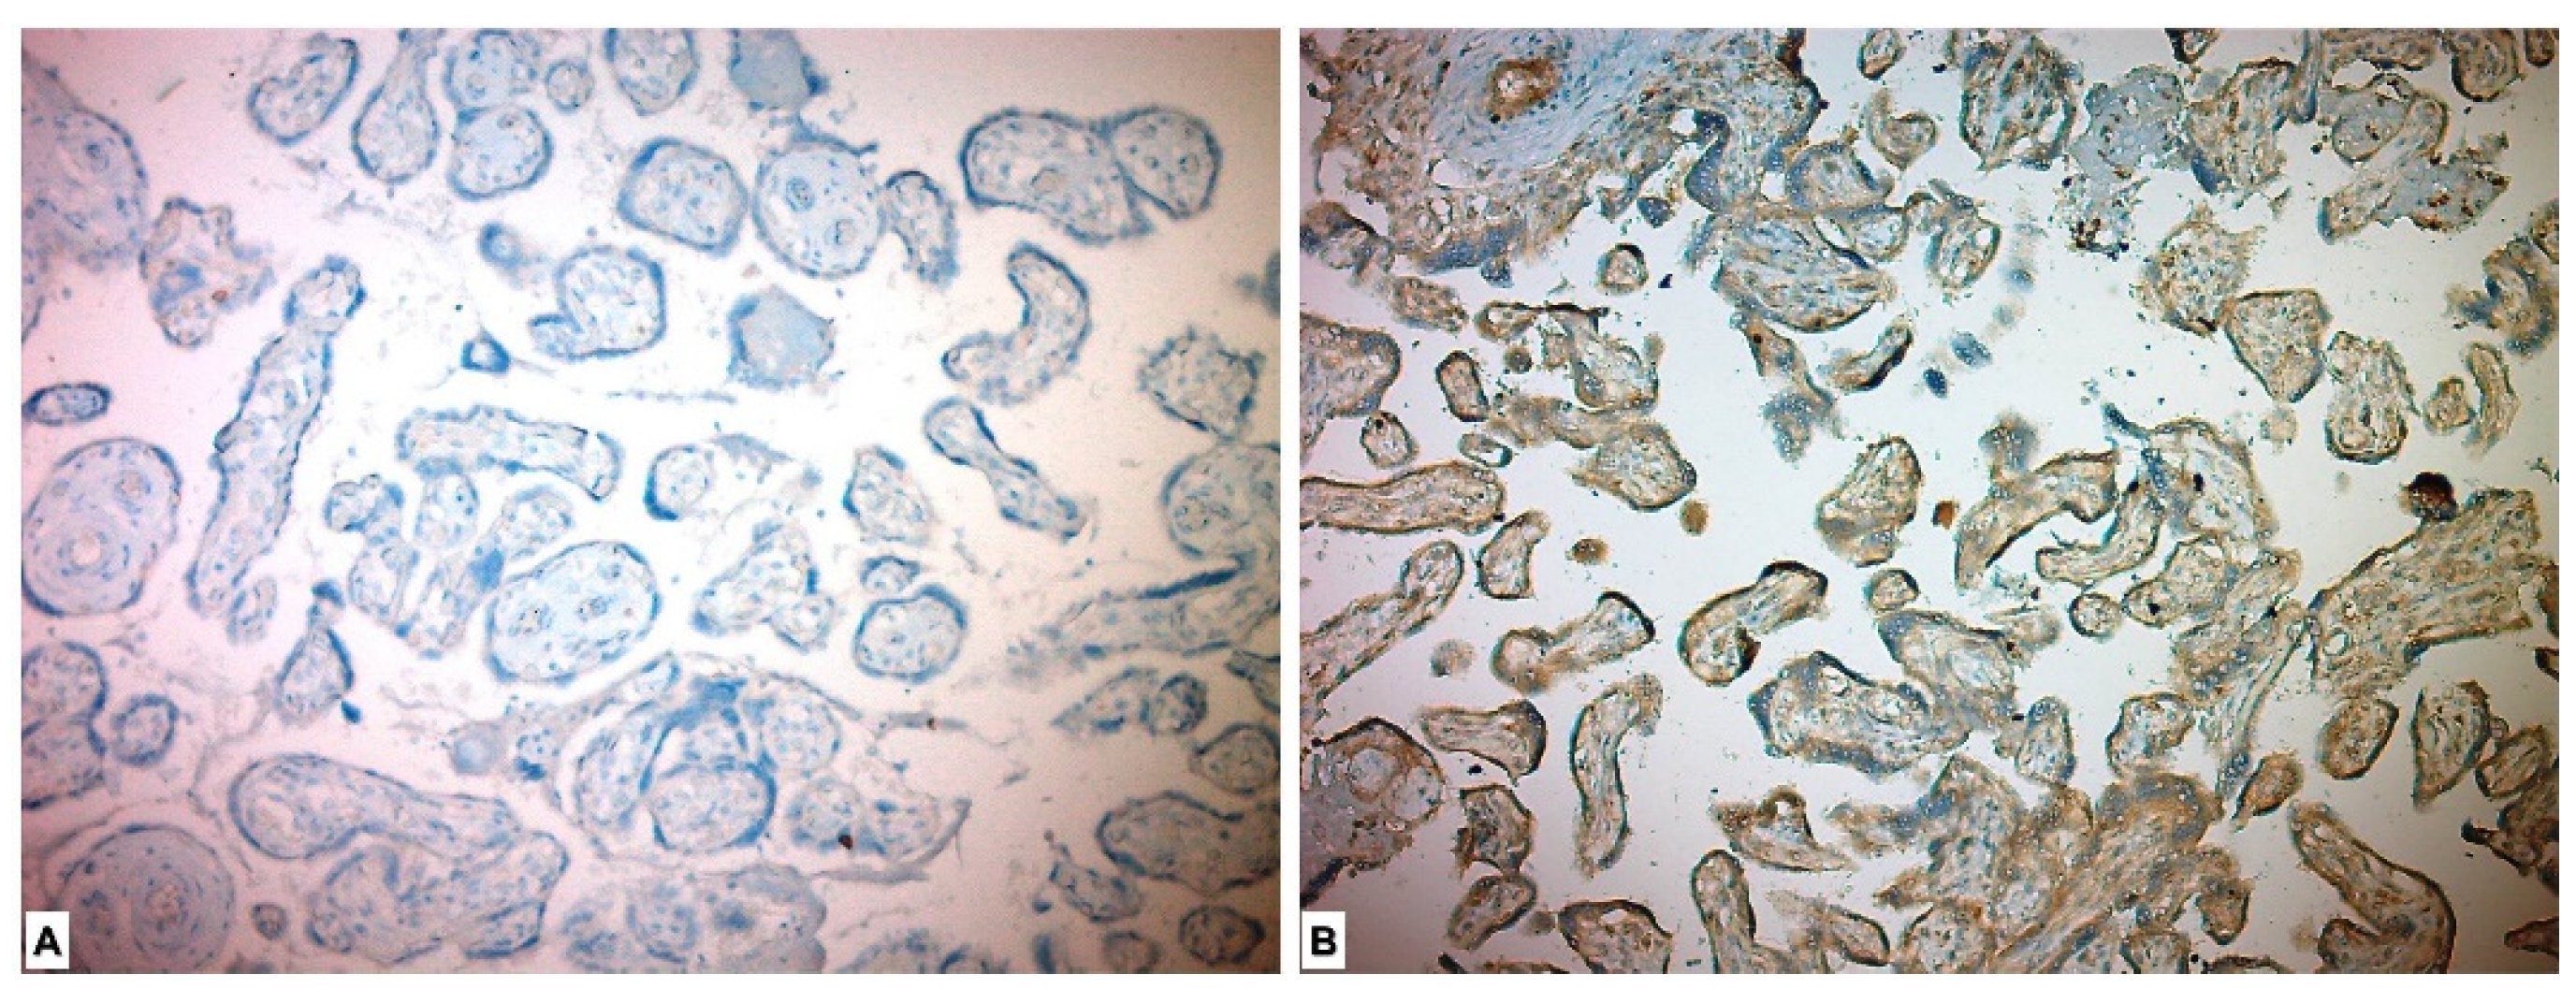

3.3. Immunohistochemical Results

| CD56 n (%) | <0.001 * | ||

| High Expression | 29 (51.8) | 0 | |

| Low Expression | 27 (48.2) | 43 (100) | |